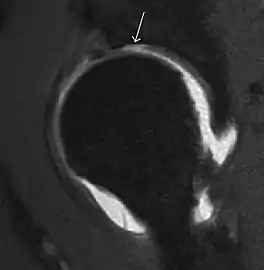

Most of the angles and measurements described in the plain radiograph section can be accurately reproduced on MRI. In addition, the superiority of MRI resolution with intra-articular contrast allows detection of labral and chondral abnormalities that may influence the choice of medical, percutaneous, or surgical management (Figure 9).[1]

Figure 9:

Sagittal T1 weighted image showing anterosuperior labral tear.[1]

MR arthrography has proven superior in accuracy when compared to native MR imaging. It is considered the best technique to assess the labrum. Knowledge of the normal variable morphology of the labrum helps to differentiate tears from normal variants. A triangular shape is most commonly seen in 66% of asymptomatic volunteers, but round, flattened, and absent labra can also be found in asymptomatic populations. MR arthrography has demonstrated sensitivity over 90% and specificity close to 100% in detecting labral tears. Loose bodies are demonstrated as filling defects surrounded by the hyperintense gadolinium.[1]